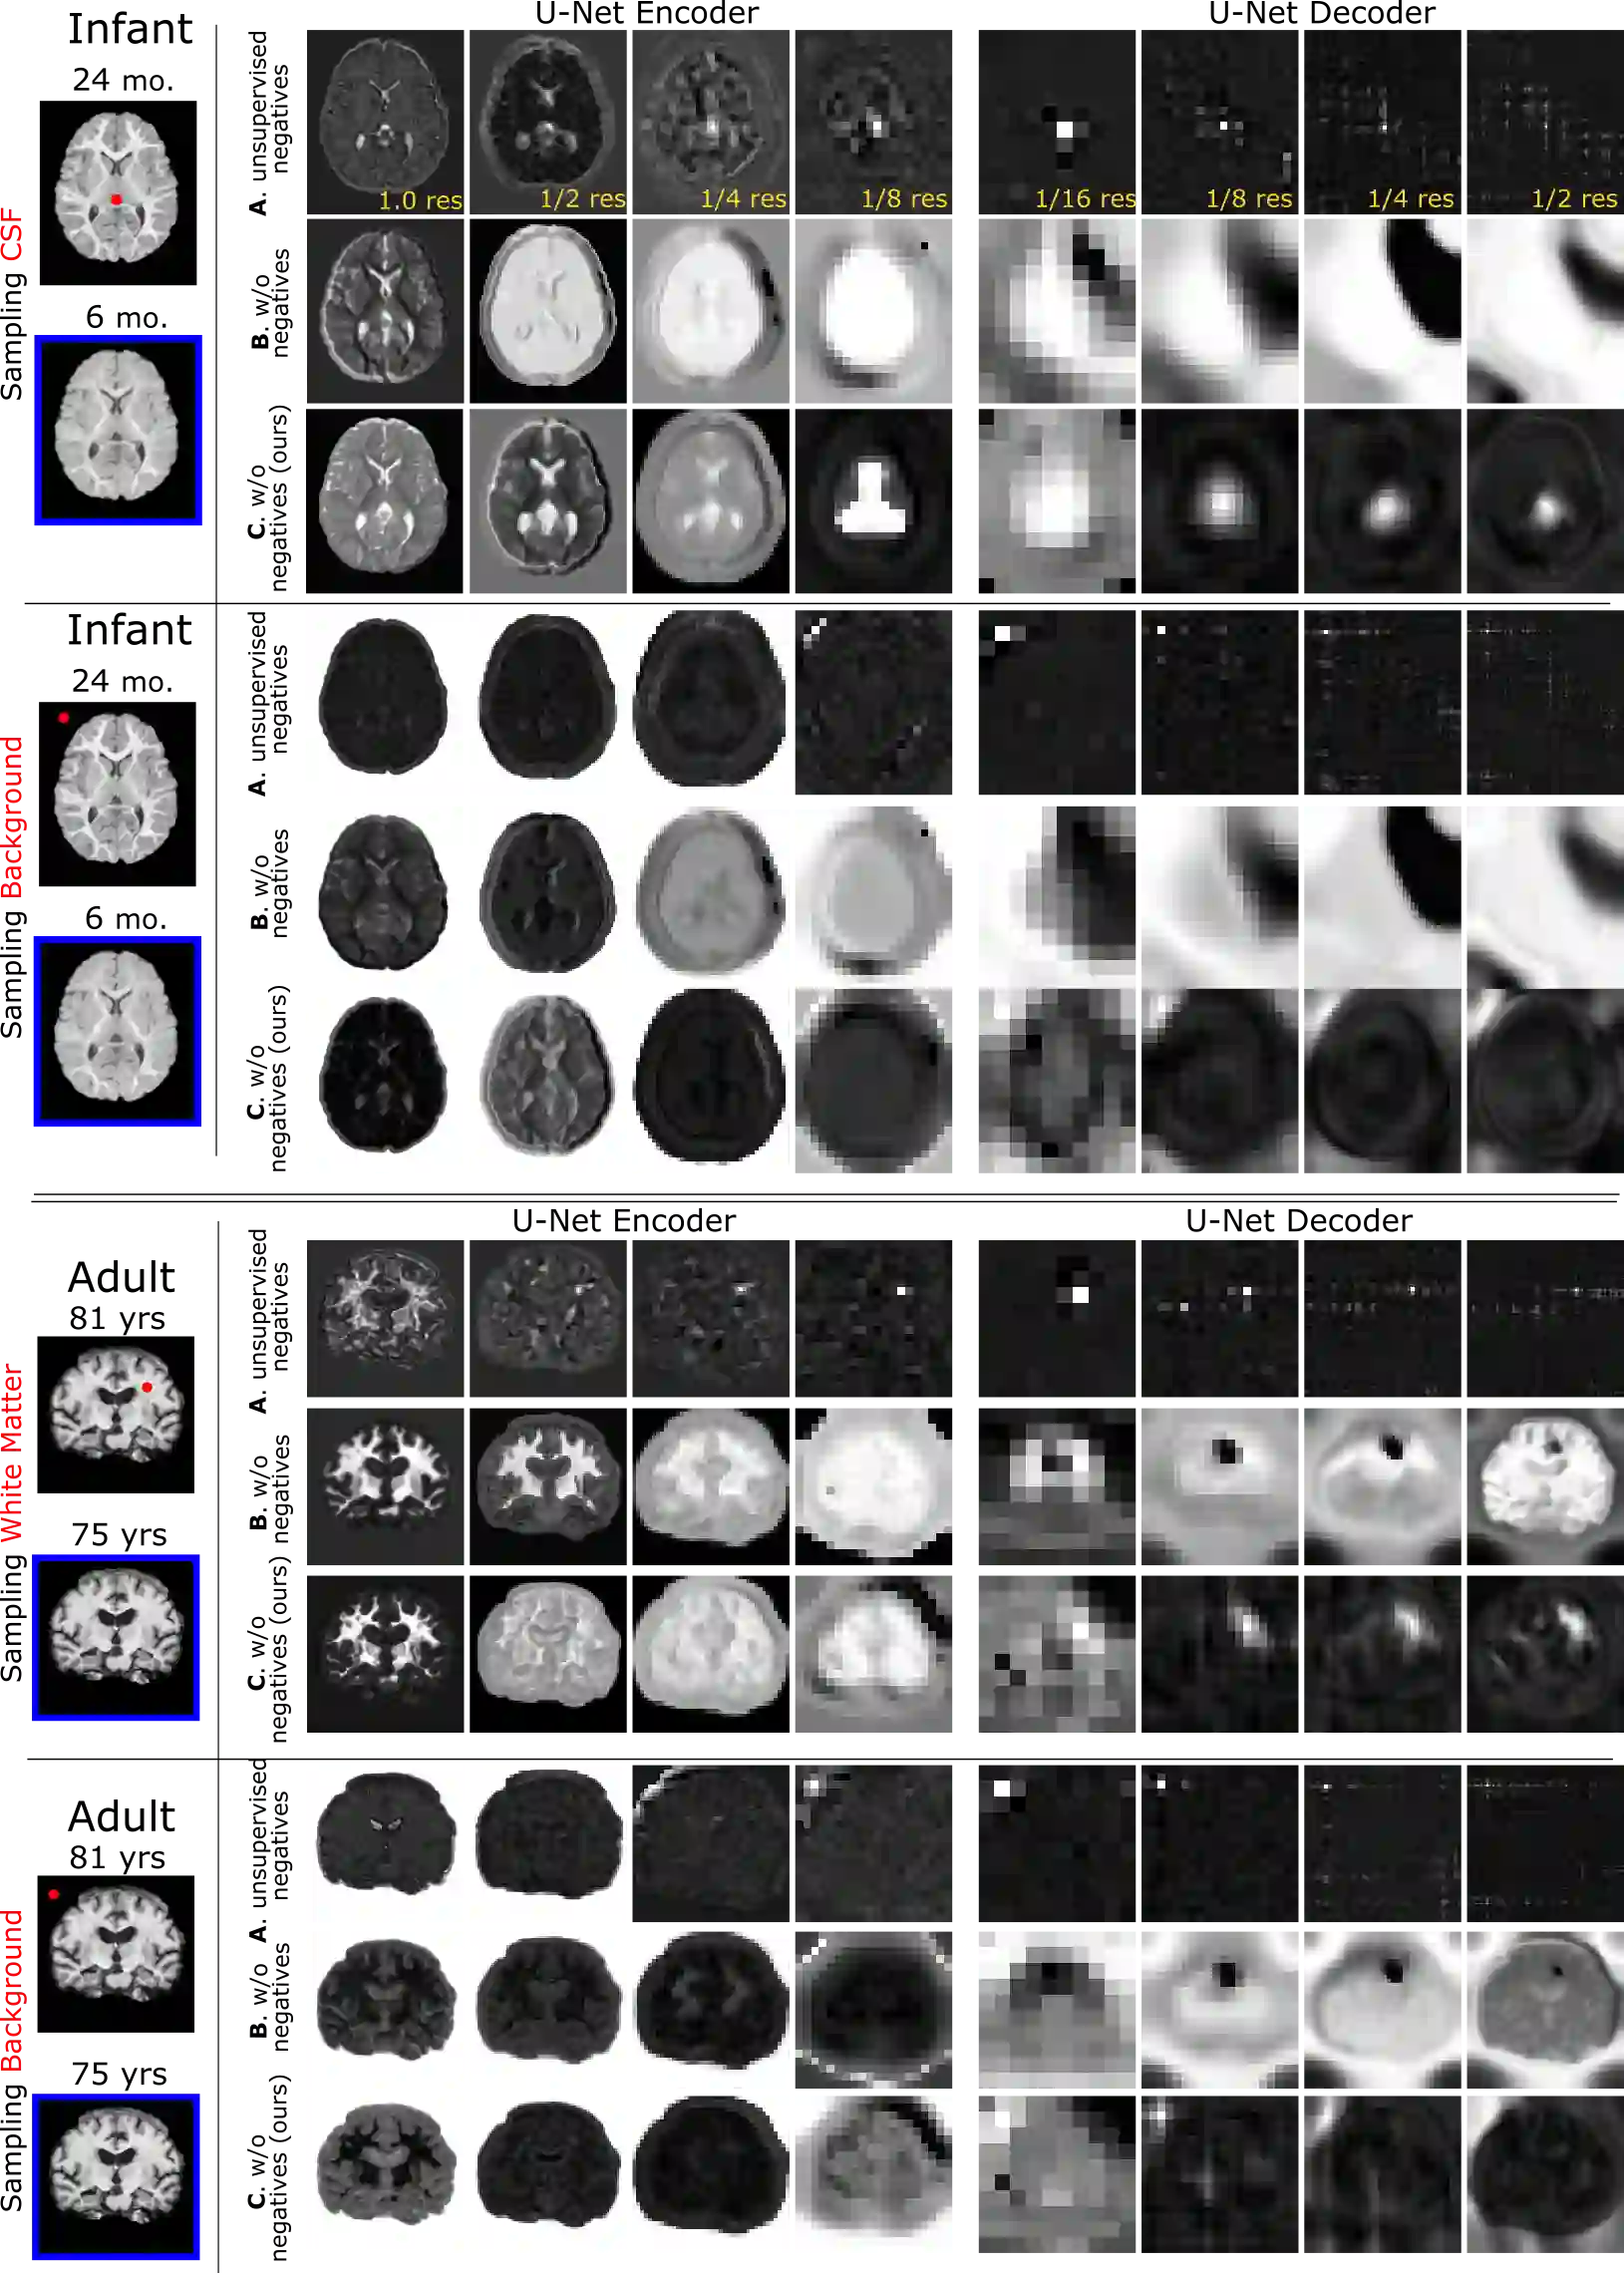

Recent self-supervised advances in medical computer vision exploit global and local anatomical self-similarity for pretraining prior to downstream tasks such as segmentation. However, current methods assume i.i.d. image acquisition, which is invalid in clinical study designs where follow-up longitudinal scans track subject-specific temporal changes. Further, existing self-supervised methods for medically-relevant image-to-image architectures exploit only spatial or temporal self-similarity and only do so via a loss applied at a single image-scale, with naive multi-scale spatiotemporal extensions collapsing to degenerate solutions. To these ends, this paper makes two contributions: (1) It presents a local and multi-scale spatiotemporal representation learning method for image-to-image architectures trained on longitudinal images. It exploits the spatiotemporal self-similarity of learned multi-scale intra-subject features for pretraining and develops several feature-wise regularizations that avoid collapsed identity representations; (2) During finetuning, it proposes a surprisingly simple self-supervised segmentation consistency regularization to exploit intra-subject correlation. Benchmarked in the one-shot segmentation setting, the proposed framework outperforms both well-tuned randomly-initialized baselines and current self-supervised techniques designed for both i.i.d. and longitudinal datasets. These improvements are demonstrated across both longitudinal neurodegenerative adult MRI and developing infant brain MRI and yield both higher performance and longitudinal consistency.